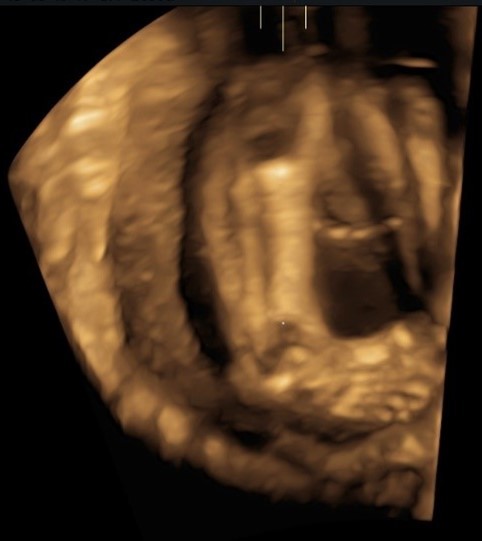

La diagnosi di piede torto può essere posta durante la gravidanza mediante l'esame ecografico che, in epoca prenatale, può identificare circa l'80% dei casi di piede torto (fig.2).

Sebbene il sospetto diagnostico di piede torto possa essere posto in una fase precoce della gravidanza, il periodo ideale per la diagnosi è il trimestre tra la 20° e la 24° settimana di gestazione, periodo in cui si esegue l'ecografia morfologica. Il piede appare deviato medialmente ed è disposto a formare un angolo retto con tibia e perone. La diagnosi è confermata se la deformità è persistentemente visualizzata nello stesso piano in cui si visualizzano la tibia e il perone e in diversi esami, ciò per evitare di incorrere in diagnosi falsamente-positive, come può accadere in caso di malposizione del piede.